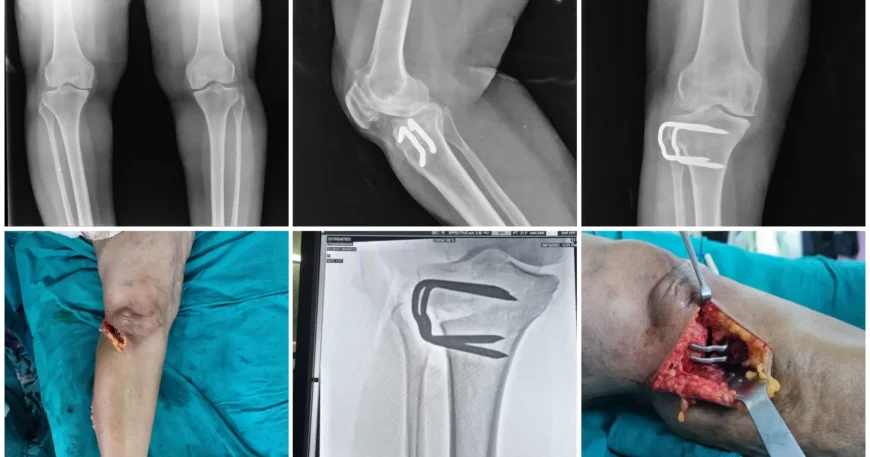

Clinical evaluation and imaging studies confirmed Medial Compartment Osteoarthritis of the Right Knee, a condition where cartilage damage is limited primarily to the inner compartment of the knee joint. This condition is often associated with varus alignment (bow-leg deformity), which increases stress on the medial compartment.

After thorough assessment, the orthopedic team recommended High Tibial Osteotomy (HTO) — a joint preservation surgery aimed at correcting alignment and reducing stress on the damaged portion of the knee.

Mrs. Virupakshamma underwent High Tibial Osteotomy, a procedure designed to:

The surgery was performed using advanced surgical planning techniques to ensure accurate correction and stable healing.